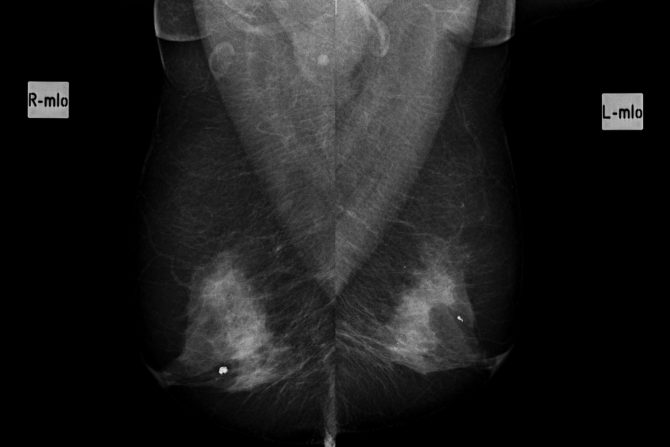

Neke promene u dojkama ne mogu se napipati samopregledom, a kalcifikati se najčešće otkrivaju mamografijom

Kalcifikati u dojkama su sitne naslage kalcijuma, koje se formiraju u tkivu dojke. Česta su pojava kod žena, posebno starosne dobi od 50 i više godina. Uobičajeno je da se detektuju tokom kontrolnih mamografskih pregleda.

Ove promene najčešće se otkrivaju mamografskim pregledom. Radiolog analizira i proučava oblik, veličinu i raspored kalcifikata. U odnosu na to određuje poreklo (da li su po njegovoj proceni benigni ili je potrebna dodatna dijagnostika.